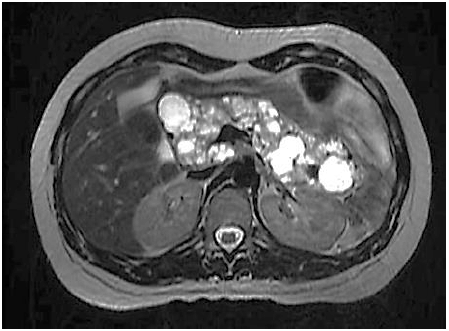

Paciente realiza ressonância magnética que individualiza múltiplas formações císticas pancreáticas conforme a imagem:

Podemos afirmar que o paciente tem maior risco de desenvolver as seguintes condições, EXCETO: